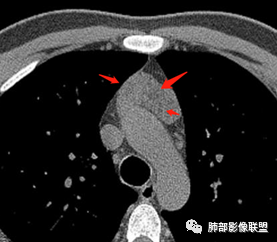

南边分析-征象标注

2、下半部分,形态自然,边缘稍膨隆,内部密度实性夹杂稍低密度影,而且是线样低密度影,比较自然走形,支持胸腺组织增生或残留。如果其他肿瘤所致,应该是边缘膨隆,类圆形,内部密度均匀,或部分区域坏死,或者结节状灶之间间隔。所以这个首先:胸腺增生或残留应该有。

* 部分区域边缘平直、稍凹陷,部分密度较低,边缘稍膨隆。

* 部分密实。因为没有增强,附近血管分不开,内部密度差不是那么明显,但是有密度差。提示:内部组织结构有变化,不是单一的组织结构。

考虑:1.发生过炎症或内部组织增生程度不一,导致各区域密度差

2.不除外合并其他病变:

①可能合并囊变

②目前的资料不能排除合并其他肿瘤性病变的可能性